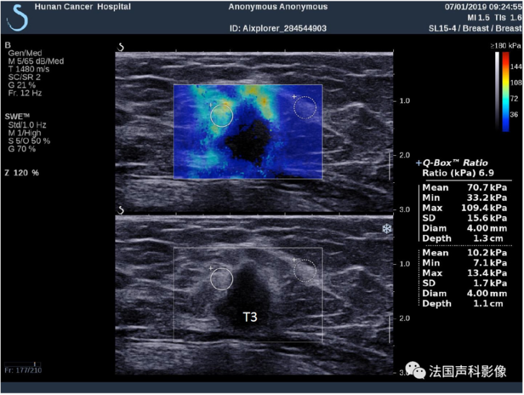

E成像还可应用于鉴别甲状腺、乳腺结节良恶性、前列腺癌及肌骨等方面, 因为同一组织中硬度的变化通常与病理改变有关,恶性组织的硬度要比正常组织硬度大得多,而弹性成像技术就是利用这一特点来区分病变的良恶性性质,给出定量数值并以此分析。根据病灶弹性不同进行分级,在二维基础上更进一步确定了良恶性,用于乳腺BI-RADS 3类及4A类结节升降类,明显提高占位性病变诊断的准确性,为下一步治疗提供了更加可靠的诊断结果,减少不必要的穿刺活检。对于乳腺非肿块型病灶因为其超声二维缺少特征性表现,往往难于判断,应用E成像定量测量并结合指南,可以为诊断提供更多依据,同理对甲状腺微小癌的检出率也大大提高。E超还用于甲状腺癌及乳腺癌等化疗的疗效评估,快速、方便、全程的监控病灶范围变小,硬度变软的变化过程,为临床化疗方案提供辅助,帮助病人更好接受并更快达到手术要求。

图3

甲状腺良恶性结节在E超下的区别(左侧结节较红-较硬;右侧结节较蓝-较软)

病灶边缘可见硬环征Emax109kPa。当乳腺病灶E成像定量测值Emax  60kpa时,需要高度提示临床,病灶恶性可能性大,建议穿刺活检